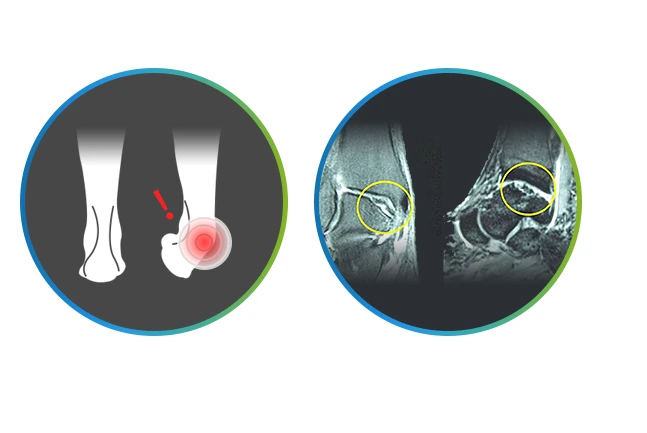

발목불안정증

발목불안정증.PNG

발목을 접질린 후 치료가 제대로 이루어지지 못한 경우에 발생하는 대표 질환으로, 평지에서도 발을 삐끗하며, 점프를 할 경우 착지할 때 불안정한 발목 쪽의 발을 간발의 시간차로 늦게 딛고, 산길과 같은 지면이 불안정한 곳에서 자주 삐끗하게 됩니다.

주로 발목이 바깥쪽으로 꺾이며, 발목을 돌릴 때 소리가 나고 뻐근한 통증이 있으며, 발에 힘이 실리지 않고 힘이 풀려 주저앉기도 해요. 또한, 걷기만 해도 통증이 느껴지기도 한답니다.

발목불안정증을 오래 방치하면 인대손상이 오래돼 인대가 두꺼워지고 덜렁거리면서 제기능을 못하기 때문에 내시경봉합술과 인대이식 등 수술을 고려해야 합니다.